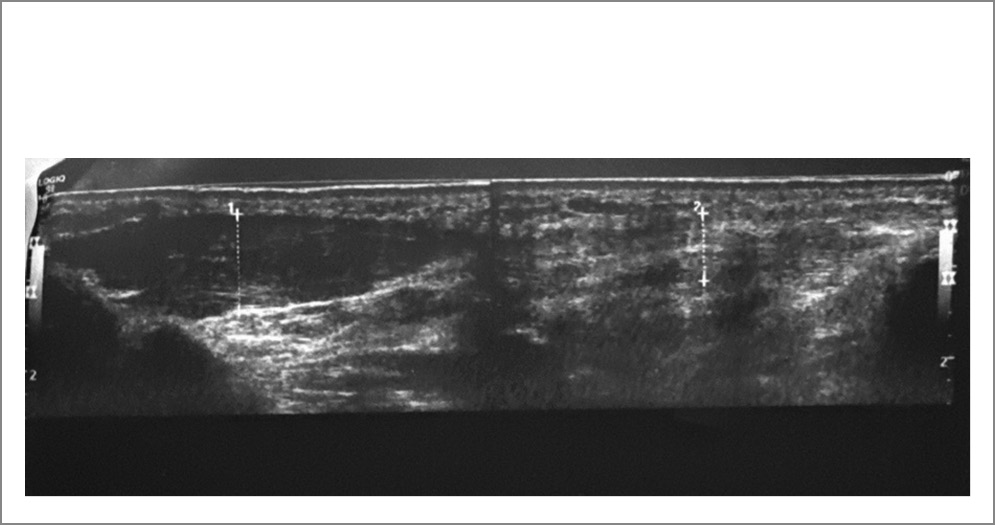

УЗИ от 06.09.2022: локтевой нерв в области средней трети плеча 7 мм2 (норма 6,55–-2,12 мм2) и нижней трети плеча 15 мм2; на предплечье: в области нижней трети 4 мм2, в средней – 4 мм2; на запястье – 3 мм2 (норма на уровне локтевого сгибателя запястья 5,91–-1,77, на запястье – 4,09+1,38 мм2); овальной формы с четким гиперэхогенным контуром и внутренней гетерогенной, упорядоченной структурой. Расположение типичное. В канале и по выходу из канала контур неровный, толщина 1,8×1,9×1,4 мм, эхогенность снижена, нарушена дифференциация, по внутреннему контуру локально, на протяжении 4 мм на глубину 0,5 мм – гиперэхогенный участок в поперечном срезе, создающий иллюзию удвоения, площадь поперечного сечения в этом участке 8 мм2, нерв уплощен. Заключение: посттравматическая нейропатия левого локтевого нерва в кубитальном канале. УЗ-картина выраженной компрессии левого локтевого нерва на уровне кубитального канала (рис. 1–3).

Рис. 3. УЗ-картина при кубитальном туннельном синдроме. Утолщенный локтевой нерв при продольном сканировании в проекции гипотенара.